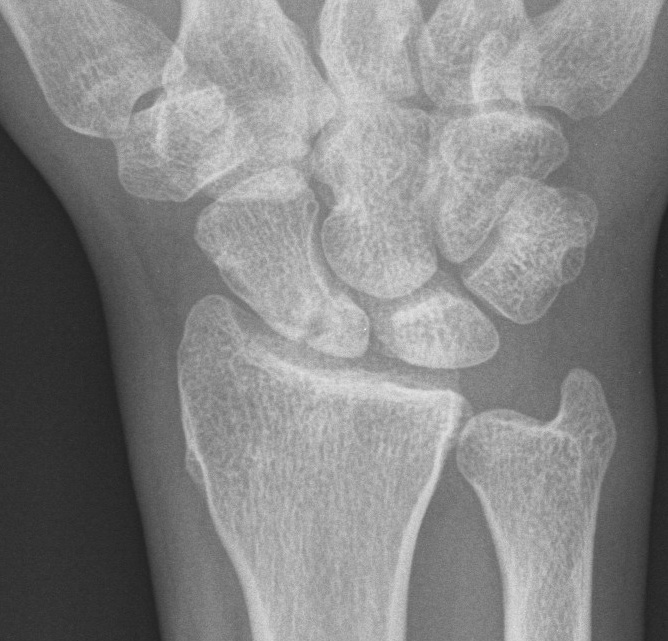

X-ray

5 images

- PA / lateral

- PA in 45° oblique pronation / PA 45o oblique supination

- PA in ulna deviation

CT

Indication: any potential displacement

Position: patient prone with fully pronated hand over head

Instability

- displacement > 1mm on any film

- intra-scaphoid angle > 35o

- comminution

- proximal pole fractures

- perilunate trans-scaphoid dislocation